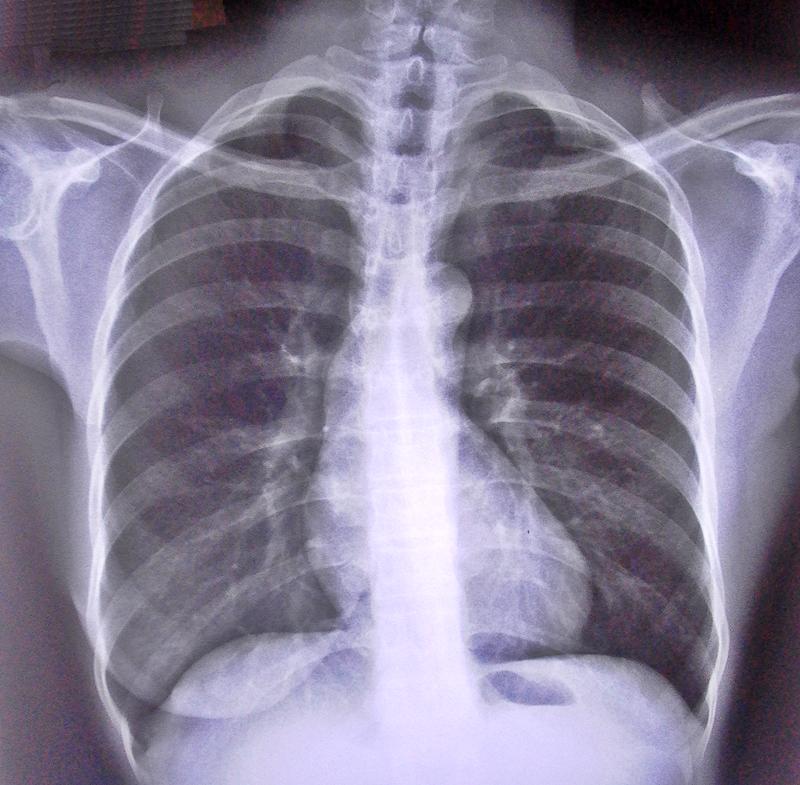

Darmowa medyczna kontrola, która odbędzie się w godz. od 9.00 do 14.00, dotyczyć będzie płuc. Wszyscy chętni będą mogli przejść badanie rentgenowskie, połączone z badaniem spirometrycznym, co pozwoli określić sprawność aparatu oddechowego. Aby poddać się kontroli, należy uprzednio wcześniej wyrazić chęć uczestnictwa w akcji. Badania przeprowadzone będą w specjalnym ambulansie, który zaparkuje tuż przy budynku Urzędu Gminy Brudzew. Kontrola stanu zdrowia zostanie wykonana dzięki – jak informują organizatorzy – nowoczesnemu, cyfrowemu aparatowi rentgenowskiemu.